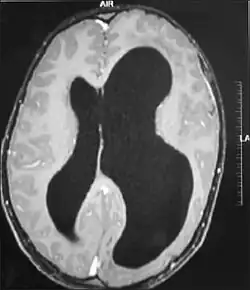

| MRI images showing megalencephaly in four family members who all have unusually large skulls (the family is affected by an autosomal recessive syndrome caused by a KIF7 mutation that induces multiple epiphyseal dysplasia)[1] | |

Megalencephaly (or macrencephaly; abbreviated MEG) is a growth development disorder in which the brain is abnormally large. It is characterized by a brain with an average weight that is 2.5 standard deviations above the mean of the general population.[2] Approximately 1 out of 50 children (2%) are said to have the characteristics of megalencephaly in the general population.[3]

A mutation in the PI3K-AKT pathway is believed to be the primary cause of brain proliferation and ultimately the root cause of megalencephaly. This mutation has produced a classification of brain overdevelopment that consists of two syndromes including megalencephaly-capillary malformation (MCAP) and megalencephaly-polydactyly-polymicrogyria-hydrocephalus (MPPH).[4] Megalencephaly is usually diagnosed at birth and is confirmed with an MRI.

A neurological exam will then be performed using the technology of an MRI machine in order to confirm the diagnosis of megalencephaly. These imaging tests give detailed information regarding brain size, volume asymmetry and other irregular developments linked with MCAP, MPPH and hemimegalencephaly.[2][21]